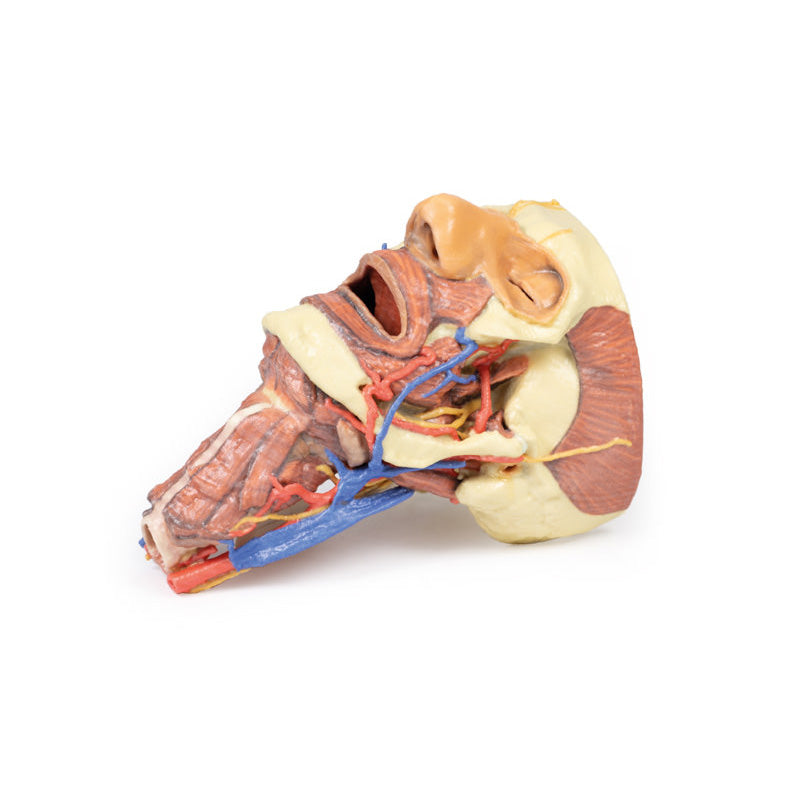

3D Printed Head and Visceral Column of the Neck

The face: On the right side of the head the parotid gland has been removed to reveal the facial nerve and all its branches (temporal, zygomatic, buccal, marginal mandibular and cervical) and demonstrate the spatial relations of structures embedded in the gland from superficial to deep (facial nerve, retromandibular vein, external carotid artery). In the surrounding region the temporalis, masseter and posterior belly of digastric are exposed, as are and the facial artery, transverse facial artery and superficial temporal artery. The facial vein and transverse facial vein are clearly visible uniting to form the common facial vein which is joined by the retromandibular vein to form the external jugular vein.

Viewed from the anterior aspect the face has been dissected to display some of the facial muscles around the mouth (buccinator [on the left], orbicularis oris and zygomaticus major). On the left side of the infratemporal fossa has been open to expose the medial and lateral pterygoids.

The lateral pterygoid is divided to show the mandibular division of the trigeminal nerve dividing into the lingual nerve and the inferior alveolar branch. Also on the left side the branches of the ophthalmic division of the trigeminal that supply the skin above the eyebrows and scalp (supraorbital [left only] and supratrochlear nerves [both sides]) are dissected. The submandibular gland is clearly visible below the mandible on both sides as are the facial arteries and veins as they course over the mandible.

The neck: The musculoskeletal portion of the neck have been removed to display the pharynx posteriorly, the larynx anteriorly, and the neurovascular bundles laterally. The suprahyoid and infrahyoid muscles can be seen on the neck, as well as the cricothyroid muscle.

When looking up the length of the trachea from below, the vocal folds are visible. The hypoglossal nerve can be seen winding around the lateral surface of the external carotid artery and the external branch of superior laryngeal nerve is seen descending in the neck. The internal jugular vein, the common carotid artery and its bifurcation into external and internal carotid arteries are clearly seen on both left and right. The vagus nerve in the carotid sheath is also visible. The ansa cervicalis is visible emerging below the digastric muscle and descending on the surface of the internal jugular vein. The internal branch of the superior laryngeal nerve can be seen below the superior thyroid artery on the left. The superior thyroid artery branching from the external carotid artery is seen descending in the anterior neck. The internal branch of the superior laryngeal artery is visible on the left piercing the thyrohyoid membrane above the inferior constrictor where this muscle is attached to the hyoid bone.

Posterior view of the pharynx: The superior, middle and inferior pharyngeal constrictors are indicated on the pharynx wall. The oesophagus can be identified emerging from the lower end of the pharynx. The posterior horn of the hyoid bone acts as a useful landmark. The carotid sheath seen from behind clearly shows the vagus nerve and its pharyngeal branches on the left. The recurrent laryngeal nerve is briefly visible on the left lying medial to the inferior thyroid artery. The occipital arteries are visible as they curve around the mastoid process. The vertebral arteries are seen either side of the brainstem as they enter the foramen magnum. The cerebellum has been removed to allow the fourth ventricle to be exposed. The cut surfaces of the cerebellar peduncles are clearly visible. A large portion of the posterior inferior cerebellar artery on the right is still visible as it winds around around the brainstem.

This 3D print specimen preserves a series of features of the head and visceral column of the neck:The face: On the right side of the head the parotid gland has been removed to reveal the facial nerve and all its branches (temporal, zygomatic, buccal, marginal mandibular and cervical) and demonstrate the spatial relations of structures embedded in the gland from superficial to deep (facial nerve, retromandibular vein, external carotid artery). In the surrounding region the temporalis, masseter and posterior belly of digastric are exposed, as are and the facial artery, transverse facial artery and superficial temporal artery. The facial vein and transverse facial vein are clearly visible uniting to form the common facial vein which is joined by the retromandibular vein to form the external jugular vein.

Viewed from the anterior aspect the face has been dissected to display some of the facial muscles around the mouth (buccinator [on the left], orbicularis oris and zygomaticus major). On the left side of the infratemporal fossa has been open to expose the medial and lateral pterygoids.

The lateral pterygoid is divided to show the mandibular division of the trigeminal nerve dividing into the lingual nerve and the inferior alveolar branch. Also on the left side the branches of the ophthalmic division of the trigeminal that supply the skin above the eyebrows and scalp (supraorbital [left only] and supratrochlear nerves [both sides]) are dissected. The submandibular gland is clearly visible below the mandible on both sides as are the facial arteries and veins as they course over the mandible.

The neck: The musculoskeletal portion of the neck have been removed to display the pharynx posteriorly, the larynx anteriorly, and the neurovascular bundles laterally. The suprahyoid and infrahyoid muscles can be seen on the neck, as well as the cricothyroid muscle.

When looking up the length of the trachea from below, the vocal folds are visible. The hypoglossal nerve can be seen winding around the lateral surface of the external carotid artery and the external branch of superior laryngeal nerve is seen descending in the neck. The internal jugular vein, the common carotid artery and its bifurcation into external and internal carotid arteries are clearly seen on both left and right. The vagus nerve in the carotid sheath is also visible. The ansa cervicalis is visible emerging below the digastric muscle and descending on the surface of the internal jugular vein. The internal branch of the superior laryngeal nerve can be seen below the superior thyroid artery on the left. The superior thyroid artery branching from the external carotid artery is seen descending in the anterior neck. The internal branch of the superior laryngeal artery is visible on the left piercing the thyrohyoid membrane above the inferior constrictor where this muscle is attached to the hyoid bone.

Posterior view of the pharynx: The superior, middle and inferior pharyngeal constrictors are indicated on the pharynx wall. The oesophagus can be identified emerging from the lower end of the pharynx. The posterior horn of the hyoid bone acts as a useful landmark. The carotid sheath seen from behind clearly shows the vagus nerve and its pharyngeal branches on the left. The recurrent laryngeal nerve is briefly visible on the left lying medial to the inferior thyroid artery. The occipital arteries are visible as they curve around the mastoid process. The vertebral arteries are seen either side of the brainstem as they enter the foramen magnum. The cerebellum has been removed to allow the fourth ventricle to be exposed. The cut surfaces of the cerebellar peduncles are clearly visible. A large portion of the posterior inferior cerebellar artery on the right is still visible as it winds around around the brainstem.